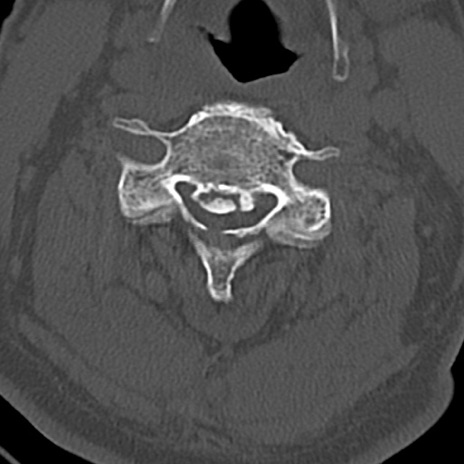

頚椎CT

横断像